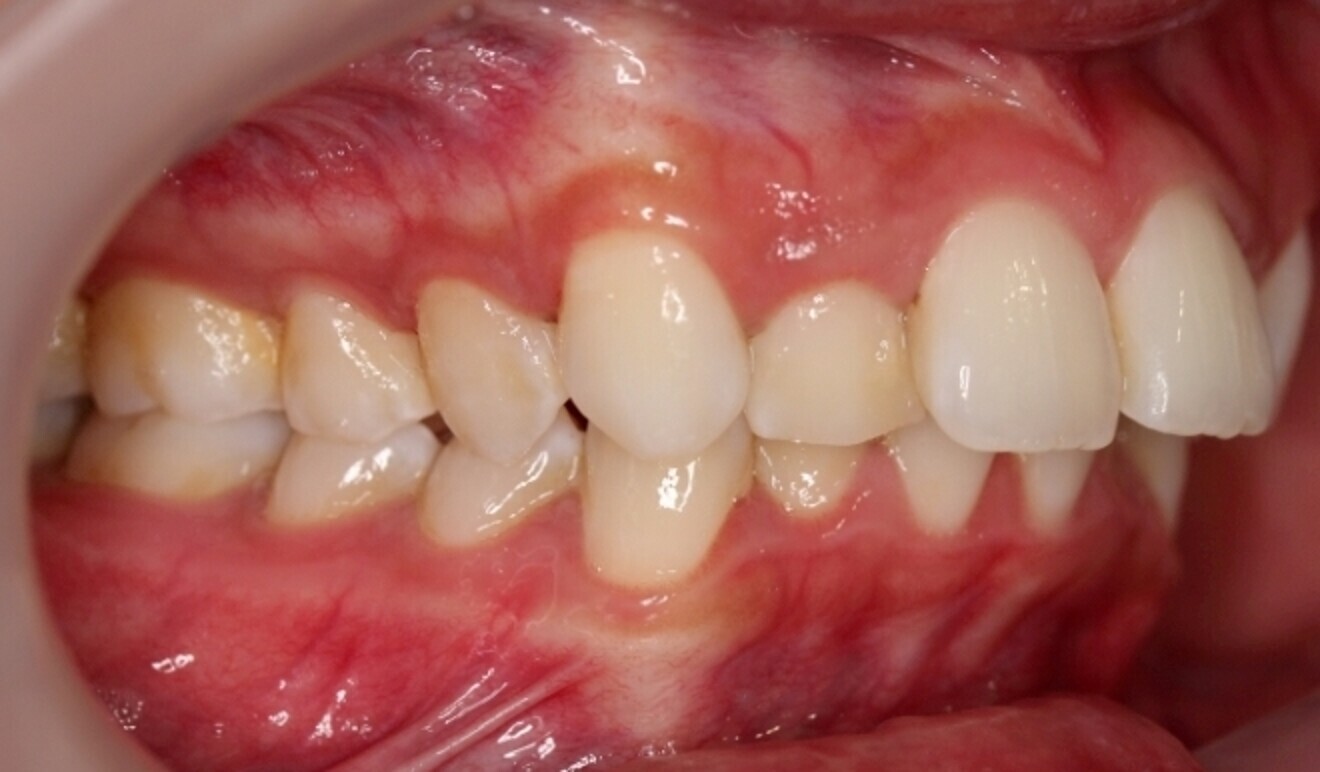

Fig. 3

The starting point for Oratomic4D was selecting a real patient to replicate. After an extensive search, the patient, Tina, was chosen for her ideal oral anatomy and range of treatments that could be simulated. Unlike a typodont model, Tina had mild crowding, impacted maxillary and mandibular third molars, and complex root canal anatomy (Figs. 2–7).

These irregularities in Tina’s oral anatomy made her an ideal candidate for the creation of a range of realistic simulation models that are highly representative of the types of patients encountered in dental practice.